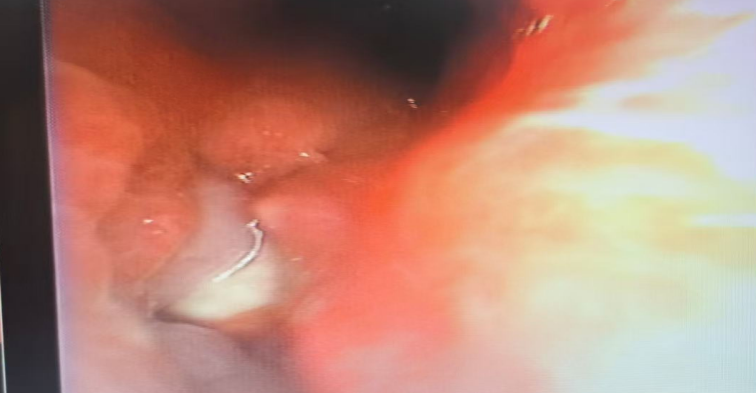

然而,情况远比想象中复杂和危险。这枚花生并非“安静”地待在气道里,而是在近一个月的“潜伏”中,引发了孩子身体的强烈排异反应——气道黏膜长出肉芽组织,将异物完全包裹。这不仅大大增加了取出难度,更导致了主气道的水肿和狭窄,严重威胁着孩子的呼吸。

这无疑是对医生技术的巨大考验。最终,凭借精湛的气管镜技术,医疗团队成功将这枚“惹祸”的花生完整取出,为孩子清除了这颗“定时炸弹”。目前,孩子正在顺利恢复中。